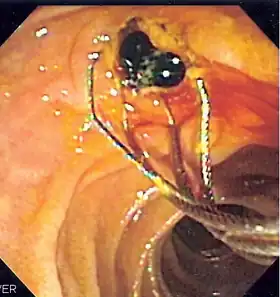

Duodenoscopic image of two black pigment stones extracted from common bile duct after sphincterotomy